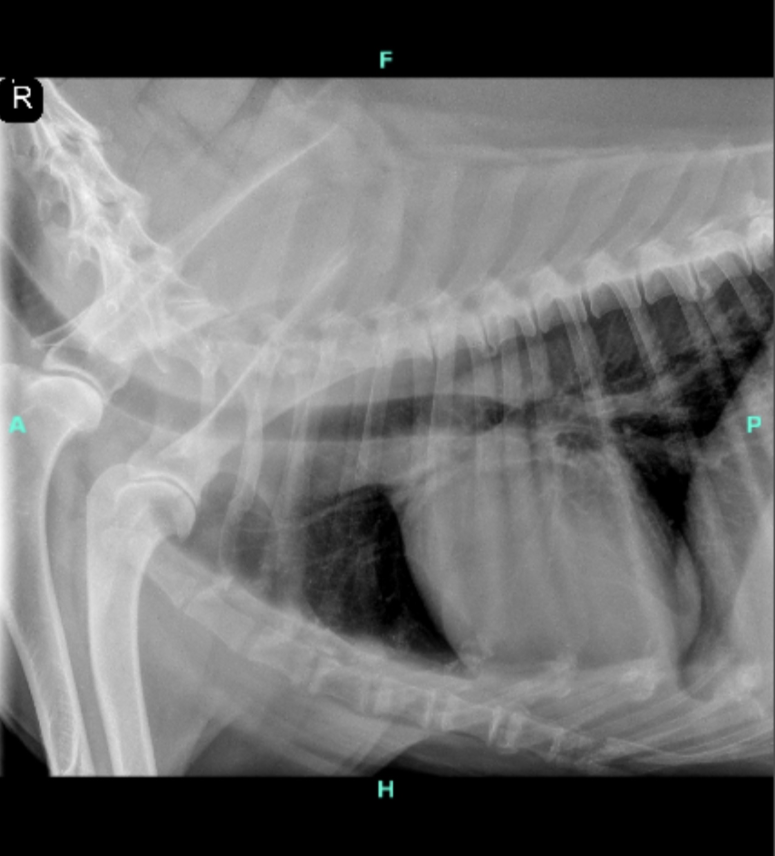

My dog Lotus, who is 11 years old, was just taken to a vet recently and I was told she has a very large tumor close to her stomach and spleen. We are not entirely sure what it's attached to, but it is extremely large. The vet says it's big enough, that it's moved her spleen out of alignment. We were told that she shouldn't be in any pain, but is very uncomfortable. We also don't know when the tumor will rupture, but were told it will happen, and now we are terrified at every moment.